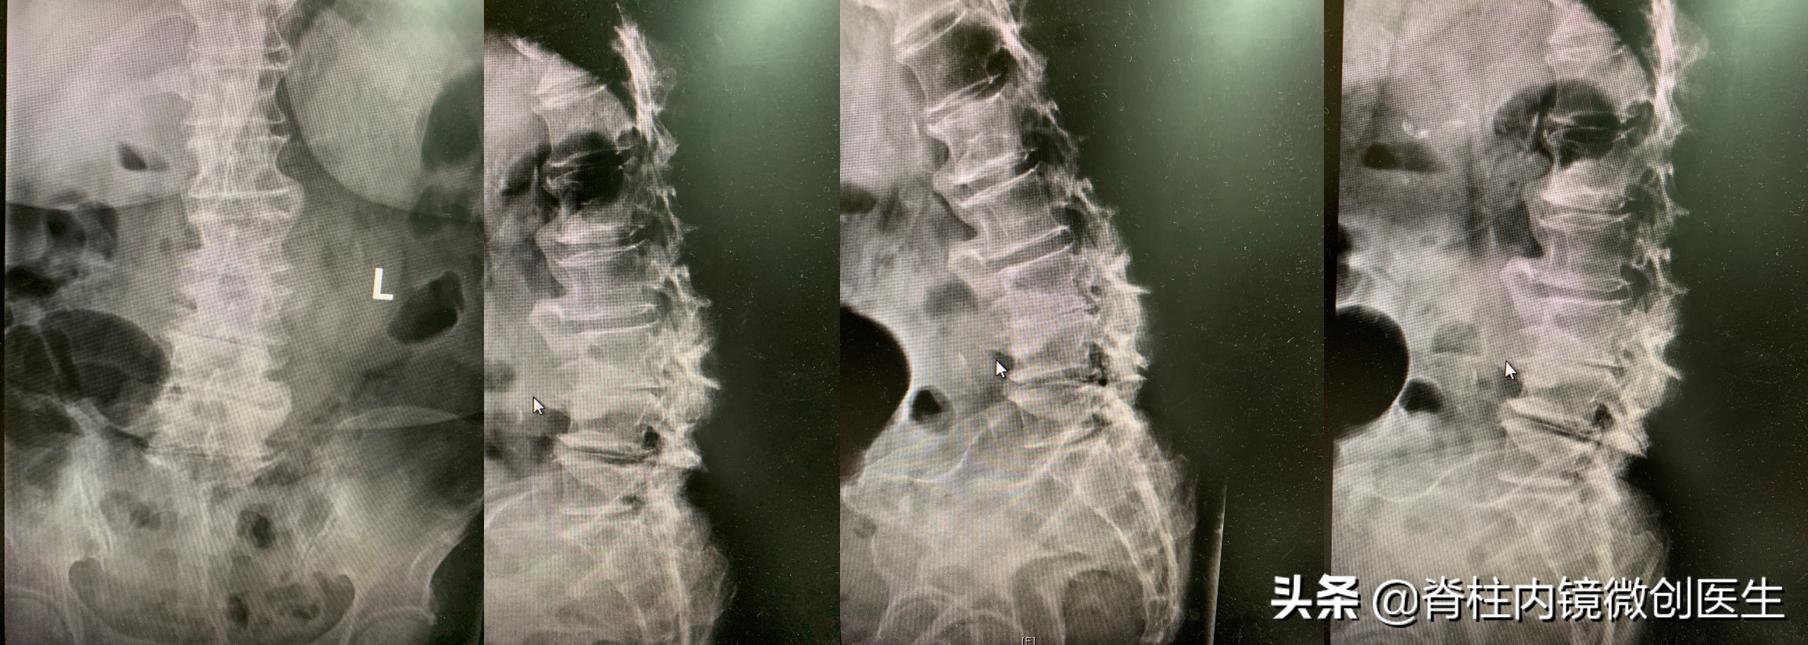

【影像学 - X光片】正位和侧位可见椎体缘及关节突增生明显,多发骨赘,屈伸位可见无明显不稳表现

腰椎X线提示严重腰椎退变,伴有椎间隙塌陷,多发骨赘形成